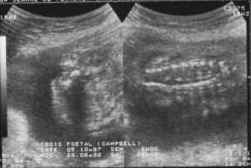

- Coupes frontales :

Ecartement des lames postérieures responsables de la perte de parallélisme du "rail spinal".

cliché droit

cliché gauche

Affleurement et renflement anormal du canal rachidien qui perd son caractère linéaire (collet herniaire).

En dehors du rachis, tuméfaction (hernie) mobile avec le foetus.